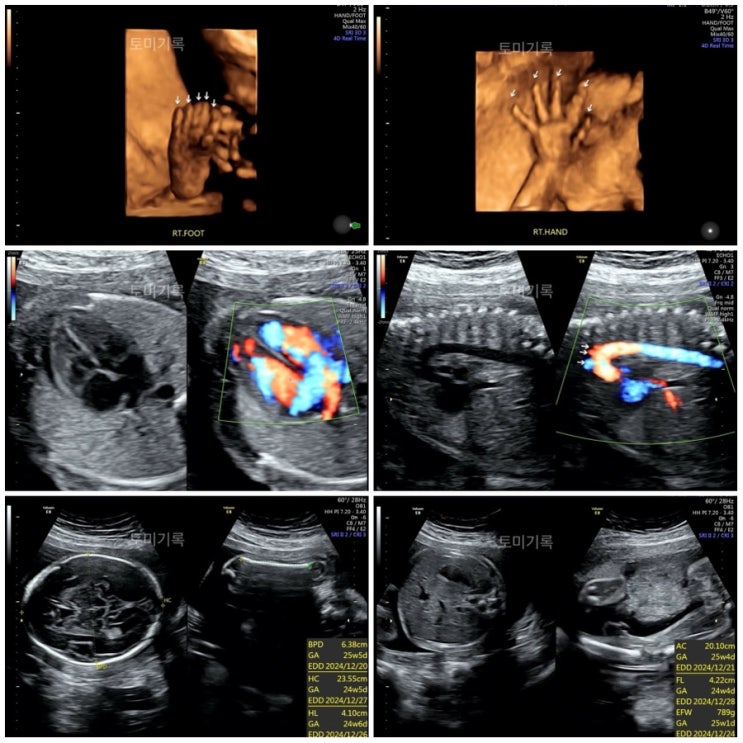

임신 24주차-26주차 기록 : 임당검사 정밀초음파 입체초음파 중기임산부 일상

임신 24주차 정기검진 : 임당검사 정밀초음파 입체초음파 2024.09.11(수) 개금미래여성병원에서는 24주차에...